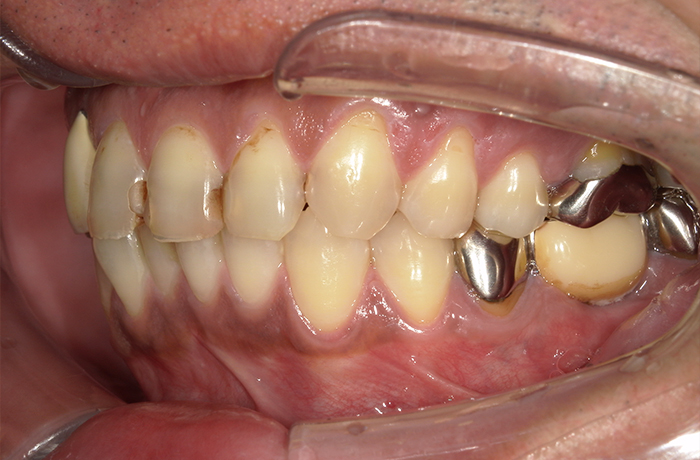

治療前後の比較

治療前

治療後